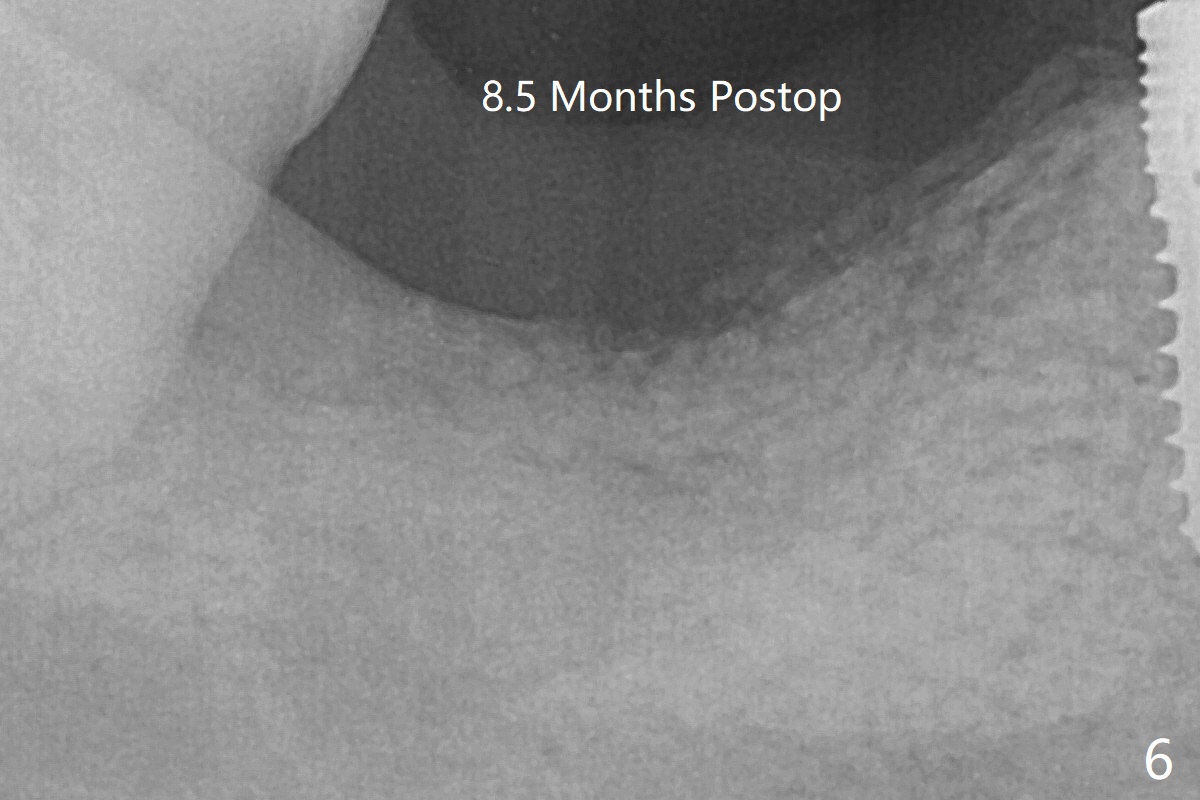

The deep soft tissue socket with hemorrhage after extraction presents difficulty in debridement of granulation tissue apically. After placement of allograft (Fig.3 *) and overlying collagen membrane (Fig.2 C), the socket is closed with 4-0 Chromic gut suture. The bone graft seems to have lost in 8.5 months (Fig.6).